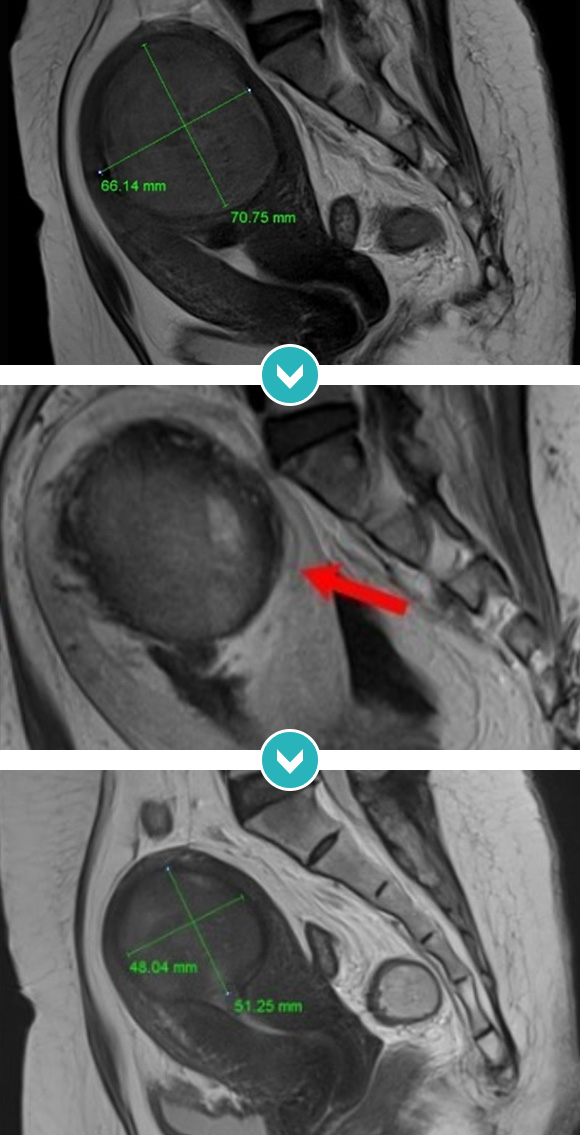

14cm 거대 자궁근종 하이푸 치료 18개월 장기간 추적관찰